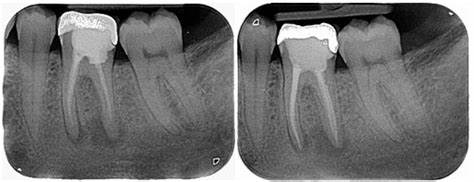

Tratamiento de conducto

Es un tratamiento que consiste en la remoción de la pulpa dental con fines de salvar o preservar un diente en boca al remover tejido nervioso muerto o afectado por alguna lesión traumática o cualquier otro factor.

Retratamiento de conducto

El retratamiento de conducto implica limpiar nuevamente los conductos dentales, debido a que se generó un proceso infeccioso interno producto de una obturación defectuosa, fractura o filtración, de esta forma se evita dolor, inflamación o pérdida de la pieza dental afectada.